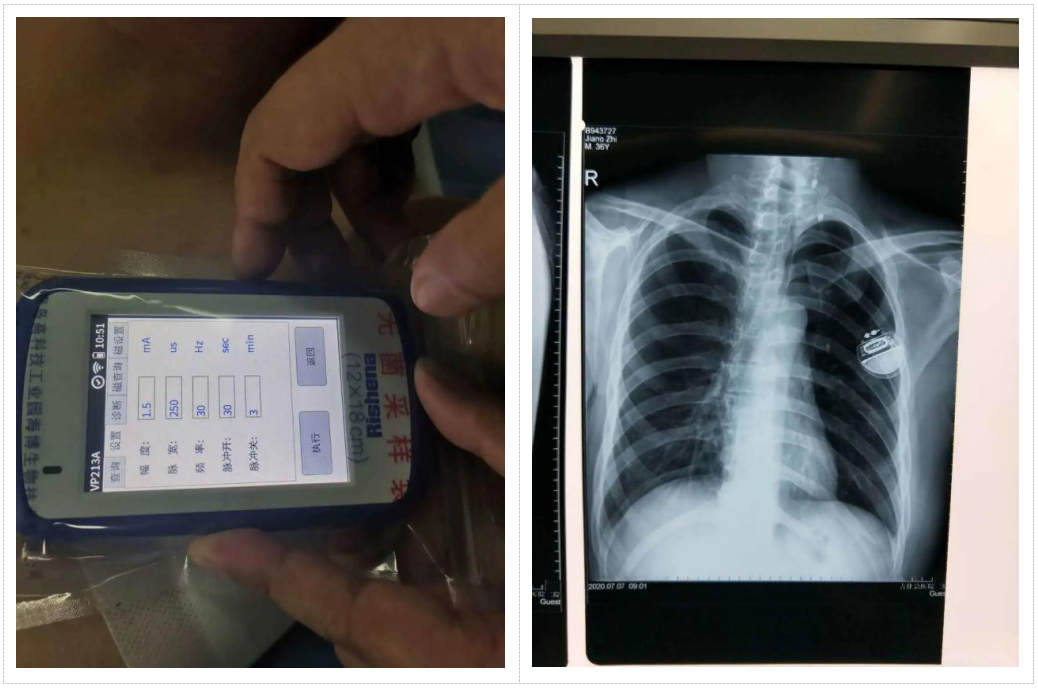

VNS疗法是通过手术将螺旋电极缠绕在患者左侧颈部的迷走神经上,并与刺激器相连接(刺激器通常放置到左肩前部)。再通过体外程控仪设置刺激器的刺激参数,刺激器按照设定好的参数发出电脉冲信号,通过电极传递到迷走神经上,传导至癫痫患者大脑,抑制癫痫发作。

VNS刺激器就像一个植入到患者体内的电子药物,它的使用寿命受到刺激参数(给药剂量)的影响。刺激器电池耗尽后,电子药物就消耗完毕,需要更换刺激器来达到续航的目的。